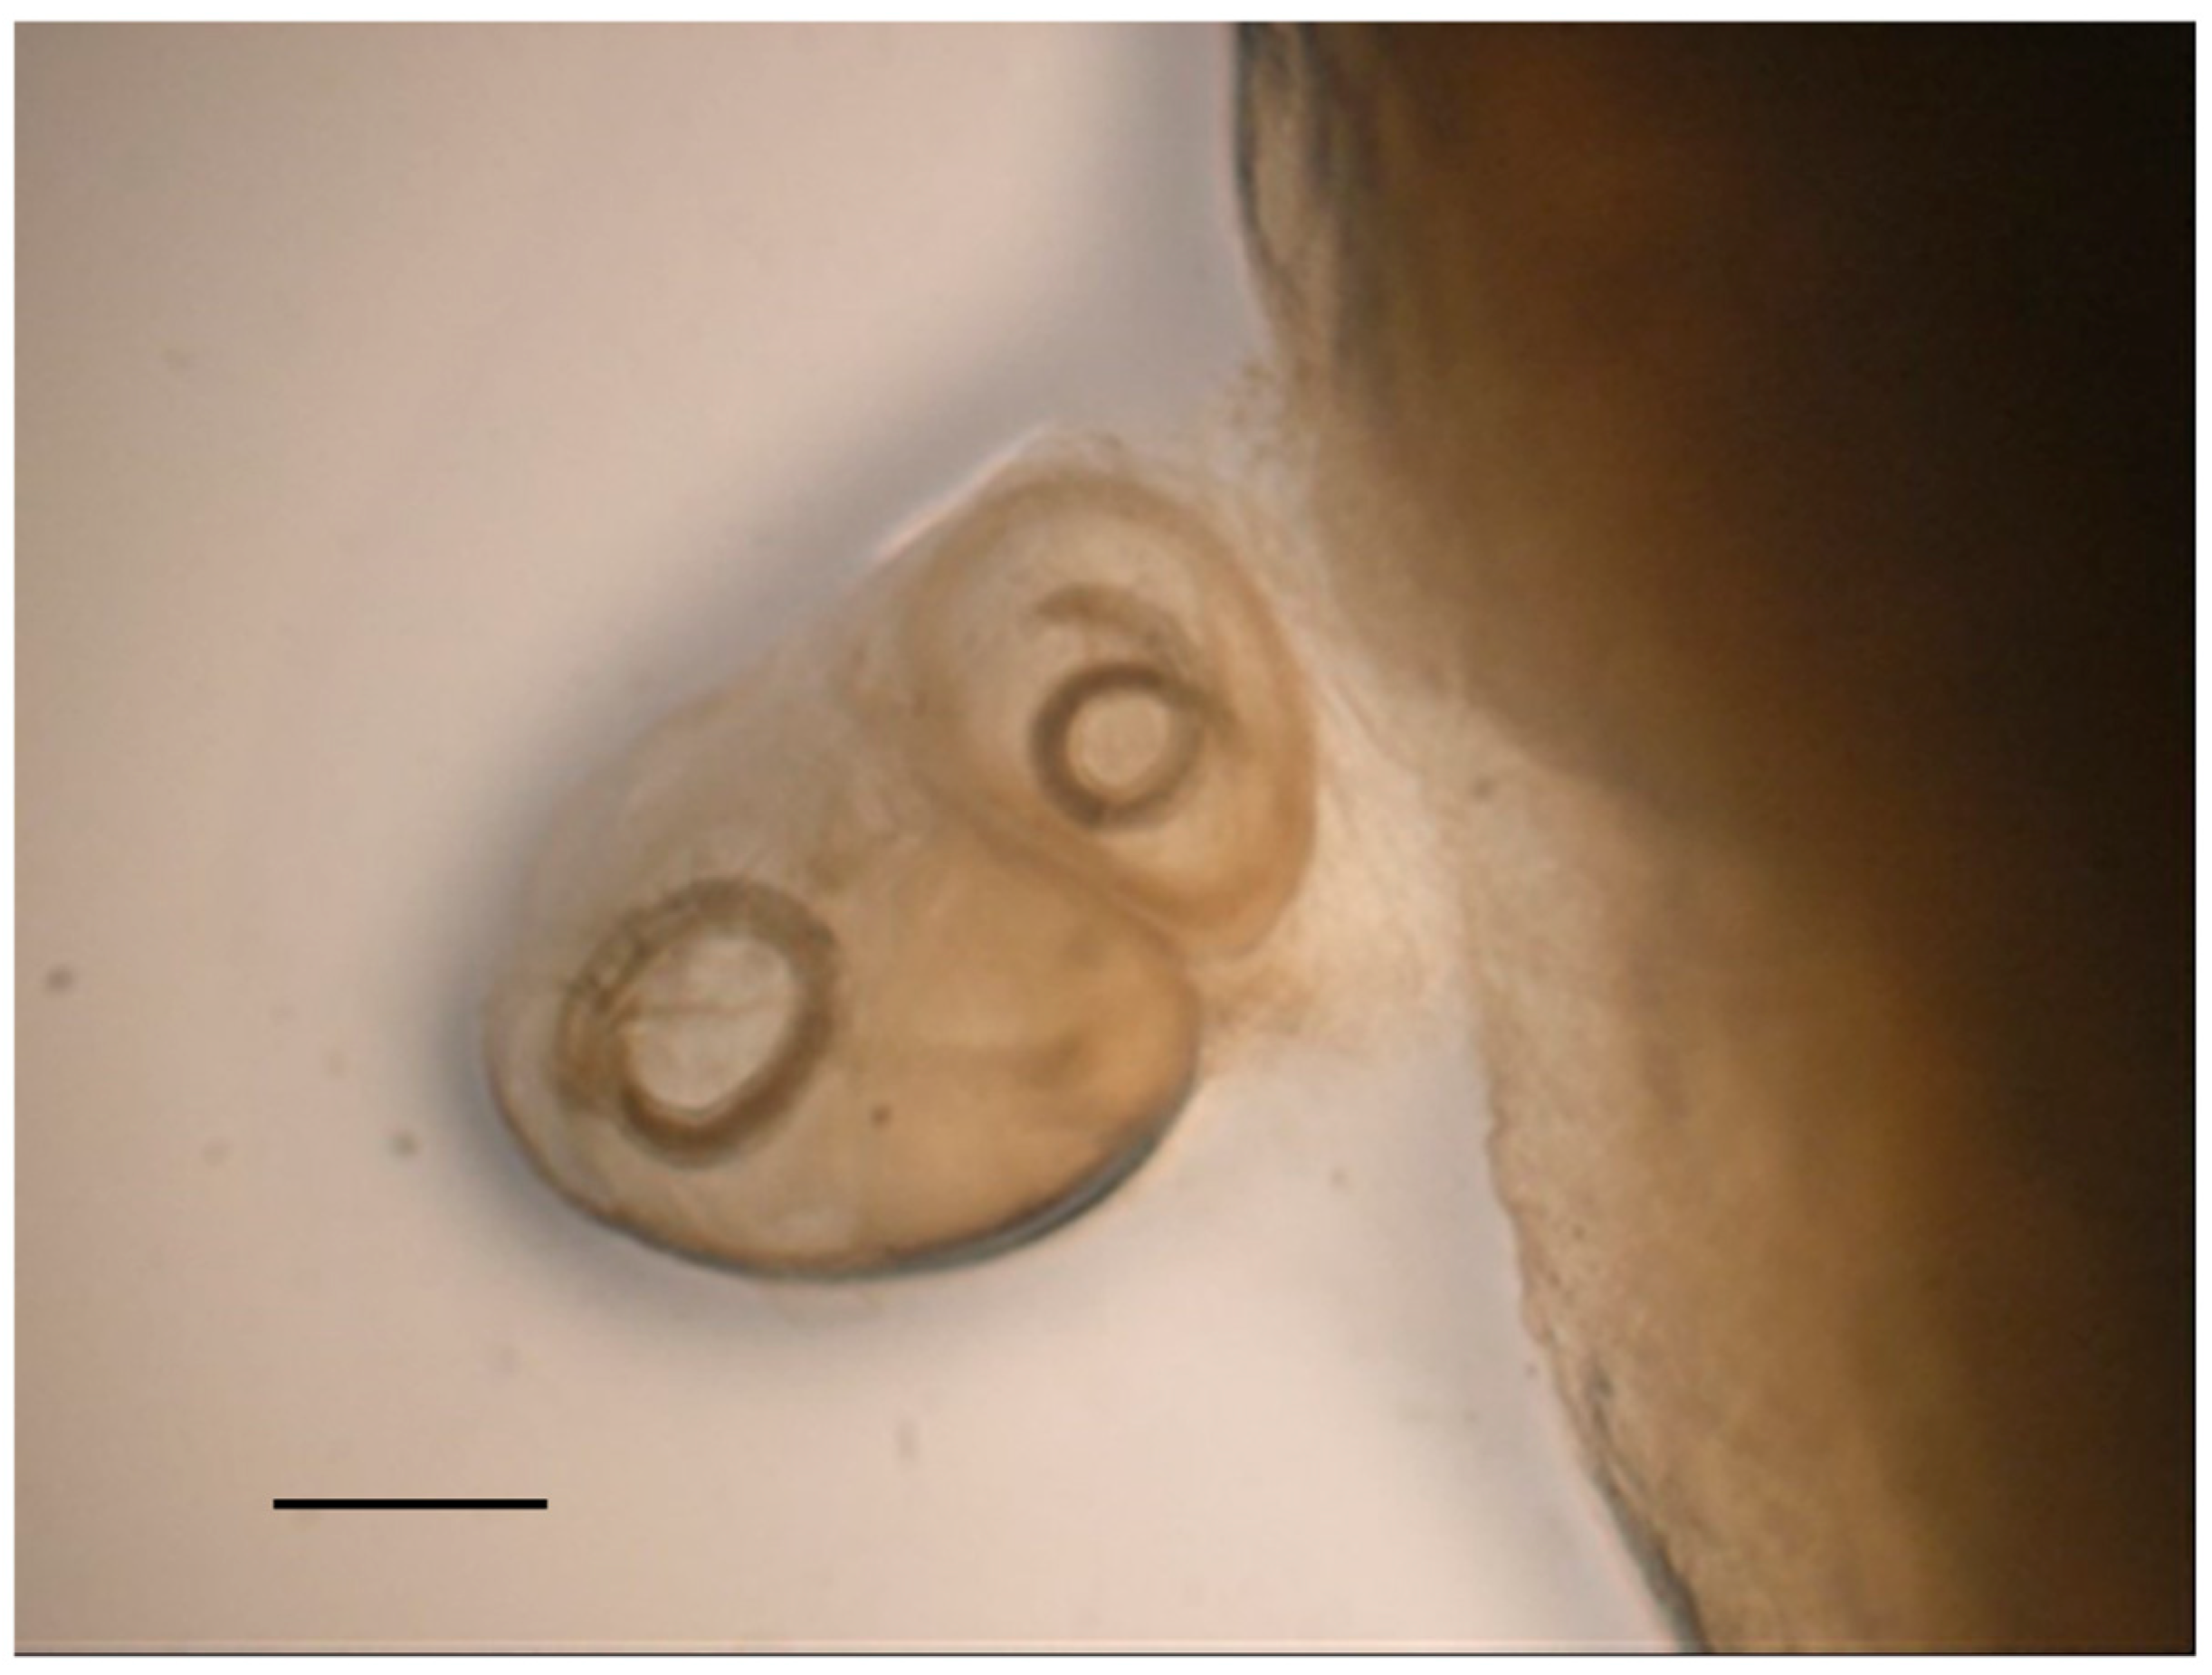

| Sparrowhawk 2 | Gizzard, Proventriculus, Intestine | Baruscacapillaria falconis (Nematoda: Capillariidae) 3 * Procyrnea leptoptera (Nematoda: Habronematidae) 2 * Spirocerca spp. encysted larvae (Nematoda: Thelaziidae) 3 * | - | - | - | Sarcocystis columbae (Apicomplexa: Sarcocystidae) heavy infections |